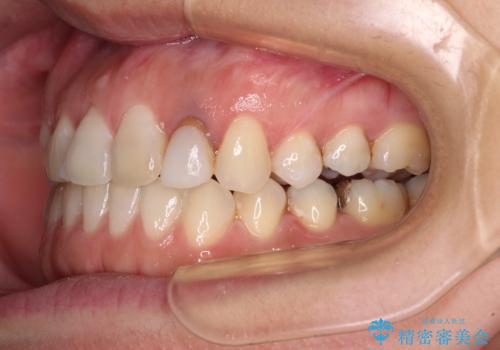

開咬と変色した前歯 インビザライン矯正とオールセラミッククラウン治療

- 前歯の開咬と失活により変色した前歯を気にして来院された患者様です。

開咬の治療は、前歯を閉じるように引っ張り出すよりも、上下臼歯を圧下(骨内にめり込ませる)させることで進める方が長期的に安定した歯列を維持できます。

インビザラインは臼歯の圧下を効果的に行えるため、インビザラインを用いて矯正治療を行うこととしました。

矯正治療が概ね終了した時点で前歯をオールセラミッククラウンにて補綴治療を行い、その後インビザラインにて細かい部分を仕上げていくことしました。